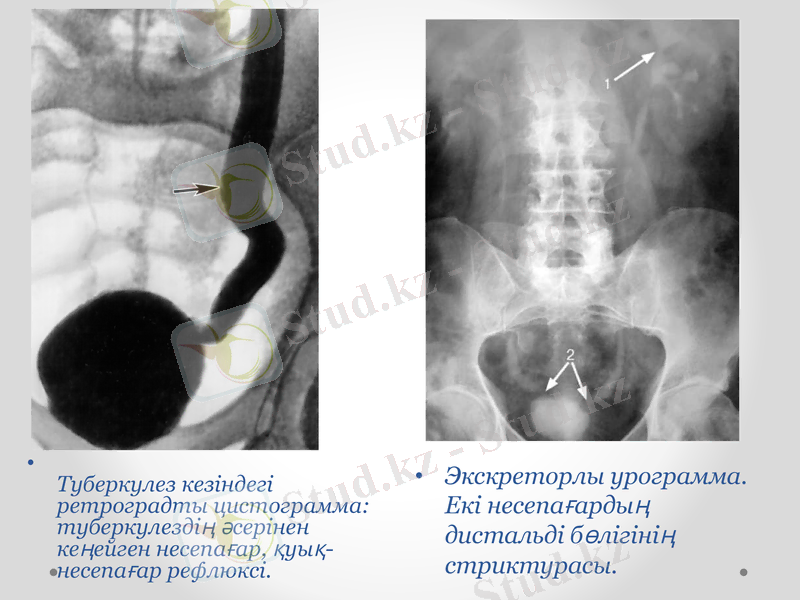

Төменгі цистограмма. Оң жақ несепағардың дистальді бөлігінің тарылуы (1) . Тыртықталған деформацияланған қуық (2) .

Экскреторлы урограмма. Екі несепағардың дистальді бөлігінің стриктурасы.

Туберкулез кезіндегі ретроградты цистограмма: туберкулездің әсерінен кеңейген несепағар, қуық-несепағар рефлюксі.